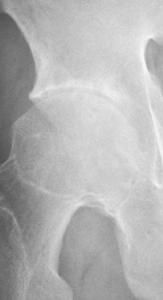

(二)X線指標

雙側骶髂關節典型改變(應排除雙側骨性關節炎)

1、雙側骶髂關節炎3~4級,加至少1項臨床指標。